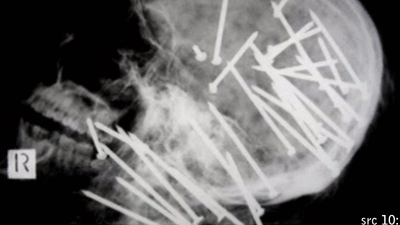

Nail Gun Murder